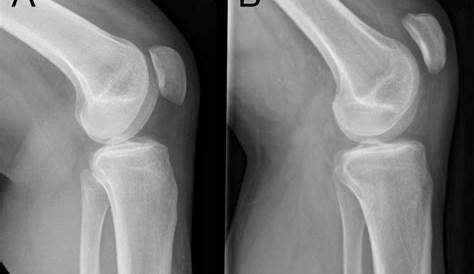

Нормальная ездовая пателла (А) и patella alta (В). © Микко Уймонен